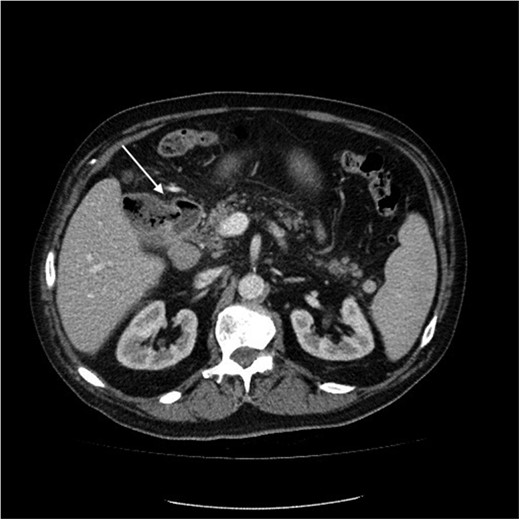

Initial upper GI endoscopy failed to enter the duodenum due to residue within the stomach with the appearance and odour of faeces noted. Abdominal computed tomography (CT) suggested a cavity with adherent ileum adjacent to the second part of the duodenum (Fig. 1). A contrast study was then undertaken demonstrating rapid flow of contrast into the terminal ileum and caecum originating from the duodenum (Fig. 2). Repeat upper GI endoscopy demonstrated an abnormal fungating fistulous communication between the duodenum and terminal ileum which permitted the full insertion of the endoscope (Figs 3 and 4). Biopsies were consistent with diffuse B-cell lymphoma (DLBCL) in accordance with the WHO classification.

Computed tomography image of duodenal-ileal mass (arrow indicates cavity).